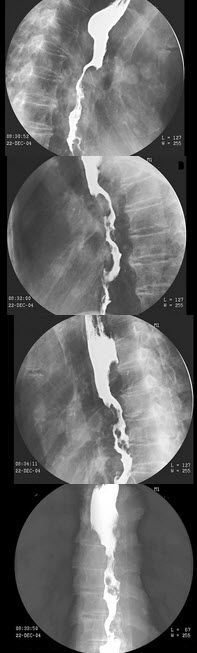

10、单项选择题

男,78岁,进行性吞咽困难1月余,结合图像,最可能的诊断为()

B.右上肋间隙变窄

女,77岁,进行性吞咽困难月余,伴胸闷气短,腹胀。结合图像,最可能的诊断为()